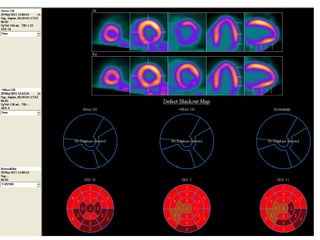

A 60-year-old male with multiple comorbid issues presented to the emergency room with chest pain. An ECG showed tall T waves and right bundle branch block. A CT/PET stress test revealed a small inferolateral infarct and significant peri-infarct ischemia. The patient was referred to cardiology to rule out acute coronary syndrome.